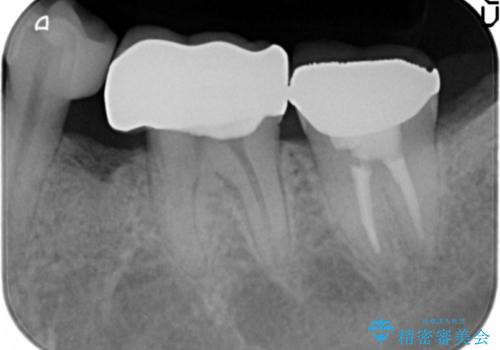

セラミッククラウンにより、抜歯した部分のスペースを閉じ歯並びを整えました。

矯正装置を用いることなくセラミッククラウンにより歯並びを整えスペースを閉じることができ、大変ご満足頂けました。

クラウンの種類:オールセラミッククラウン スタンダード